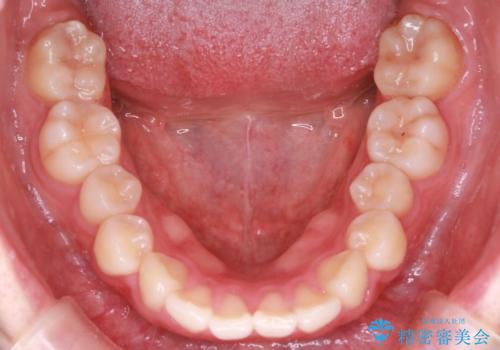

【インビザライン】前歯のねじれを治したい。

- 前歯の凸凹を主訴に来院されました。

スペースを作るために顎間ゴムを使用して、奥歯の遠心移動をおこない配列しました。